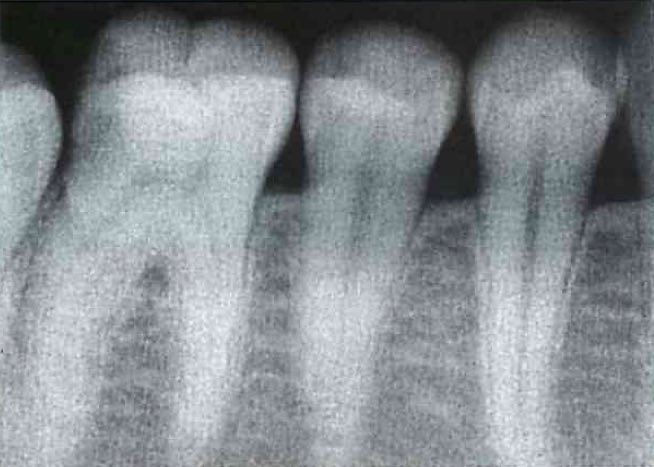

6歳の男児。定期診査を希望して来院した。来院時のエックス線写真を別に示す。

a Hellmanの歯齢はⅢA期である。

b 下顎切歯が1歯不足している。

c 犬歯の歯冠の位置は正常である。

d 下顎第二小臼歯が1歯不足している。

e 第一大臼歯の歯根形成は遅延している 。

正答 b,c

a ヘルマンの歯齢が悩みます。6も1も萠出途中だし、どっちだったっけ、ⅡCだったかⅢAだったか。。。そもそも、ⅡCとⅢAの明確な違いってなんだっけ。。。

x線の所見は本当に見慣れていないときついです。「c 犬歯の歯冠の位置は正常である。」って自身持って選べる学生は少ないと思います。臨床でがっつり症例こなしたりすると自然に身につくようなもんでしょうけど、学生で教科書にのっている数枚のレントゲンしか見ていない状態だときついものがあります。

以上を踏まえて問題のレントゲンを見てみると、、、上下6が萌出途中で、噛み合っていませんよね!ということで、これはⅢAになれていないので、ⅡCだと一発で判断することができます!

実は、国家試験の正答は間違っています。選択肢の「d 下顎第二小臼歯が1歯不足している。」が、誤答肢になっていますが、これは実は正しいです。パノラマをよく見てみると右下5の歯胚が薄くですが、でき初めています。この感じだと左下5も今後でてくる可能性は十分にあります。

御存知の通り、先天欠如の多い歯種は「8」「5」「2」ですね。それぞれ、「大臼歯」「小臼歯」「切歯」でもっとも遠心にある歯は退化傾向で、先天欠如が多いことで知られています。この問題のパノラマも「5」がその傾向にあり、下顎では歯胚の形成がすごく遅れており右下5のみ確認できます。上顎では左上5が正常に発生していますが、やはり右上5の歯胚は確認できません。

よって、本当はこの「d 下顎第二小臼歯が1歯不足している。」は微妙な選択肢で、最近の感じだと削除かこの選択肢も丸になる流れになると思います。クレームがついてもきちんとした反論はできないかと思わます。(一応、この内容は、大学の小児歯科の先生に確認とれていますし、ANSWERでは画像所見の欄にのみ指摘されています。)